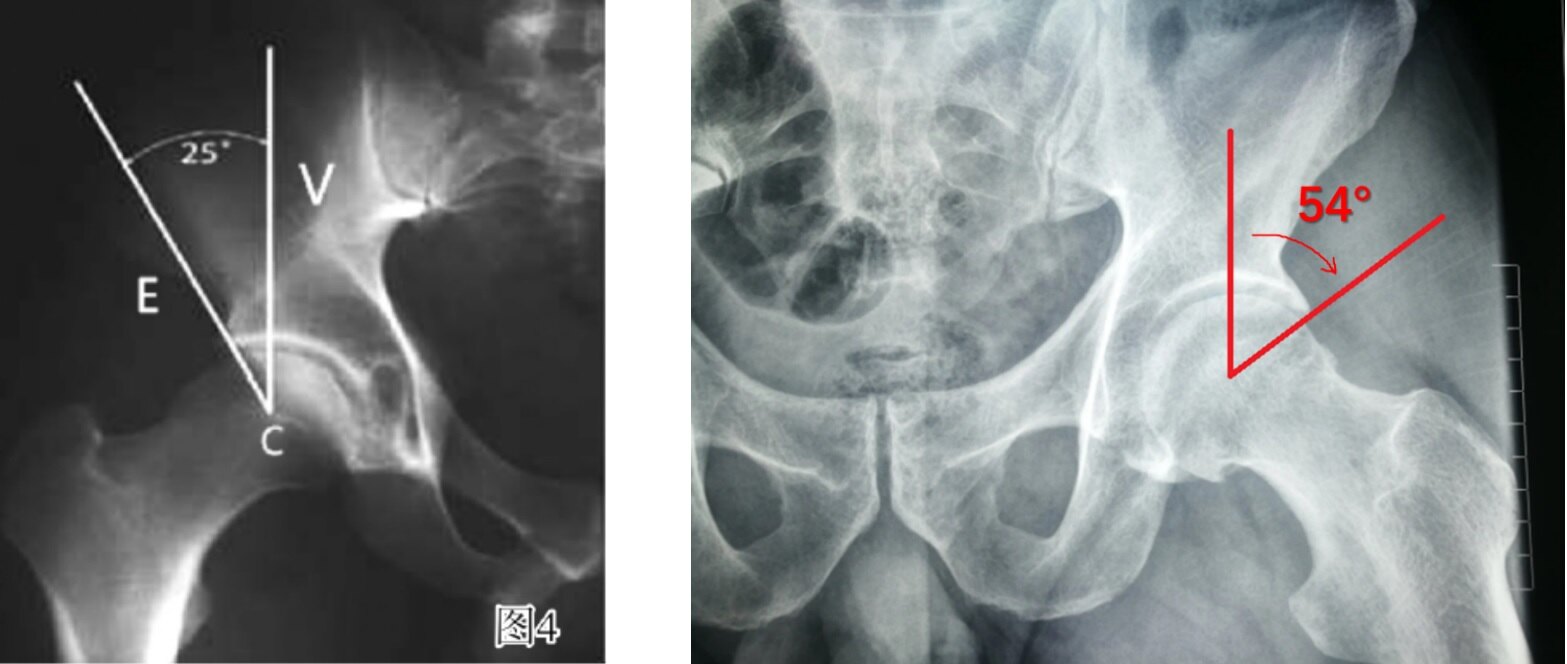

① 凸轮Cam:A. 手枪柄样畸形

B. α角增大> 50°(45°Dunn位)

②钳夹Pincer: A.外侧中心边缘角(Lateral Center Edge angle, LCE) >39°,提示髋臼外侧过度覆盖。(正常范围为25°~ 39°,<25°髋关节发育不良。)

B.髋臼后倾:髋臼前缘线位于髋臼后缘线的外侧:阳性交叉征(8字征)